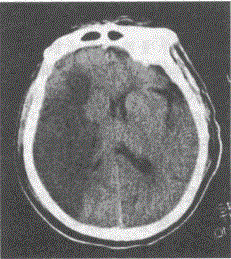

男,60岁。清晨睡醒后左侧肢体无力,刷牙时无法拿杯,有糖尿病和高血压病史无心脏病史,半天后急诊。查体:左侧肢体肌力3级,腱反射高于右侧,左侧Babins-ki征阳性。左侧肢体痛温觉减退。脑CT见下图:

本题考查目的是综合临床资料和CT图像作出脑血管的诊断。从上题的缺血性卒中与出血性卒中的鉴别要点表中很容易得出标准答案D脑血栓形成。短暂性脑缺血发作的体征一般1~2小时恢复,而且以单肢瘫等局限体征为多见。CT图像上一般没有梗死灶。脑栓塞一般在活动状态下,数秒钟即出现明显脑症状,大多数患者有房颤等栓塞灶的来源。这些均与本例不符合,故缺血后卒中以脑血栓形成为正确答案。